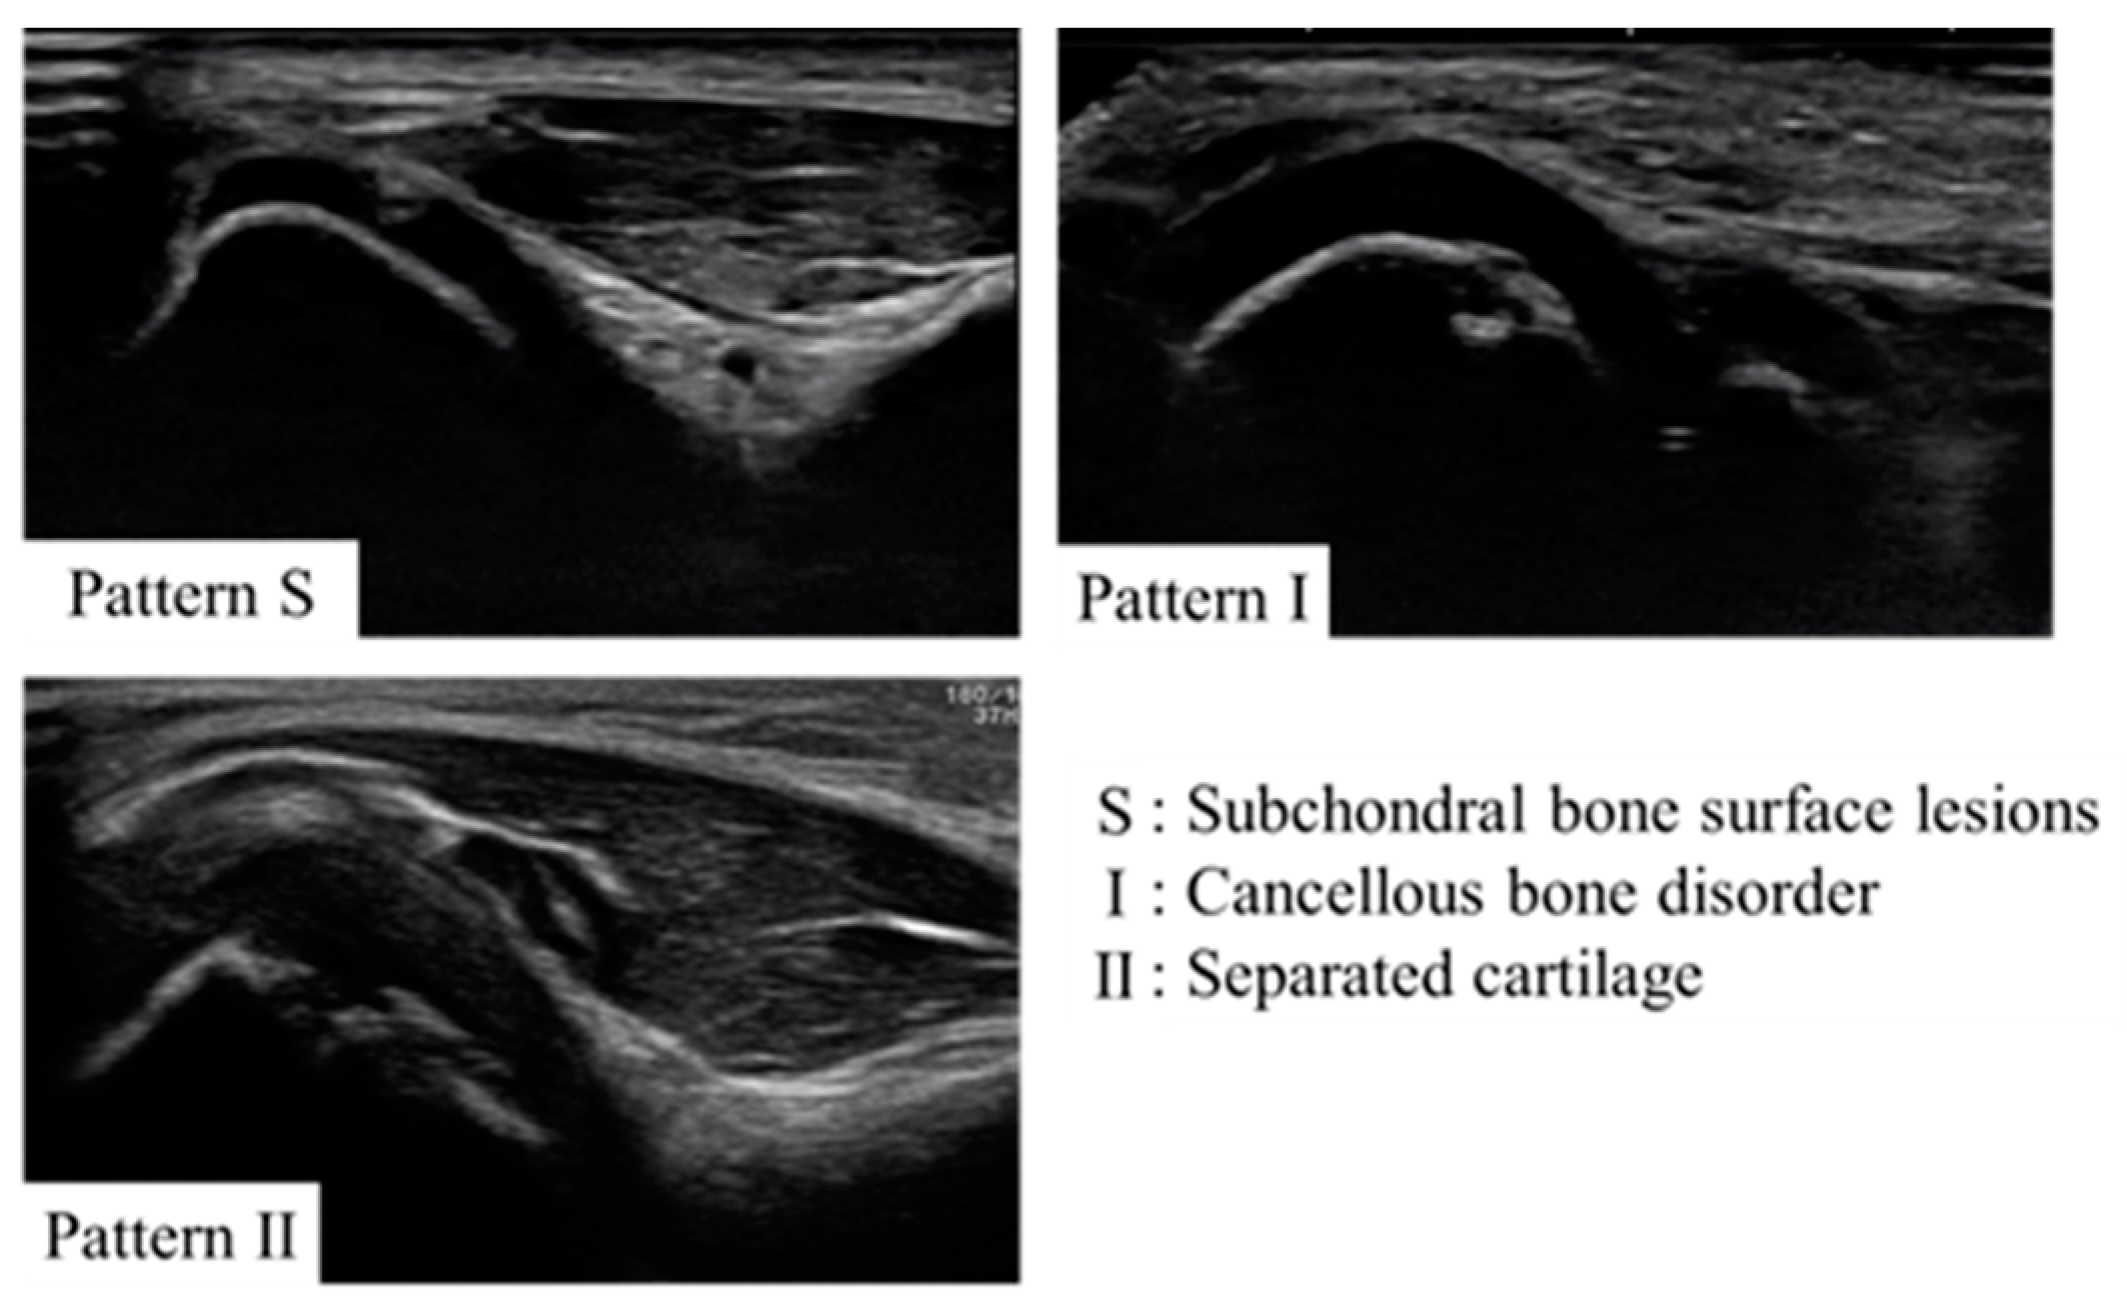

Those with complaints of elbow pain and joint tenderness were considered symptomatic. Physical examination revealed pain in 19 players, including 2 who were part of Group O. There was limited extension observed in eight players, half of whom belonged to Group O. Pain during extension was present in five players, with two being from Group O. Limited flexion was found in eight players, with two in Group O; pain on flexion was noted in four players, with none in Group O. Tenderness at the medial epicondyle was evident in 27 players, with 3 in Group O, while tenderness at the humeroradial joint was reported in 10 players, including 1 in Group O. Furthermore, tenderness at the olecranon was found in five players, with one from Group O. The valgus stress test was positive at 30 degrees of elbow flexion in 13 players, with 1 in Group O; at 60 degrees, it was positive in 16 players, with none in Group O; and at 90 degrees, it was positive in 13 patients, with none in Group O (Table 1). Of those diagnosed with OCD, five exhibited pattern S, one had pattern 1, and four presented with pattern 2 (Figure 4).

Figure 4. Ultrasound images of the lateral elbow for each case in this study. For one case (case 6), only the record was available, and the image was not preserved. Arrowheads indicate sites of OCD.